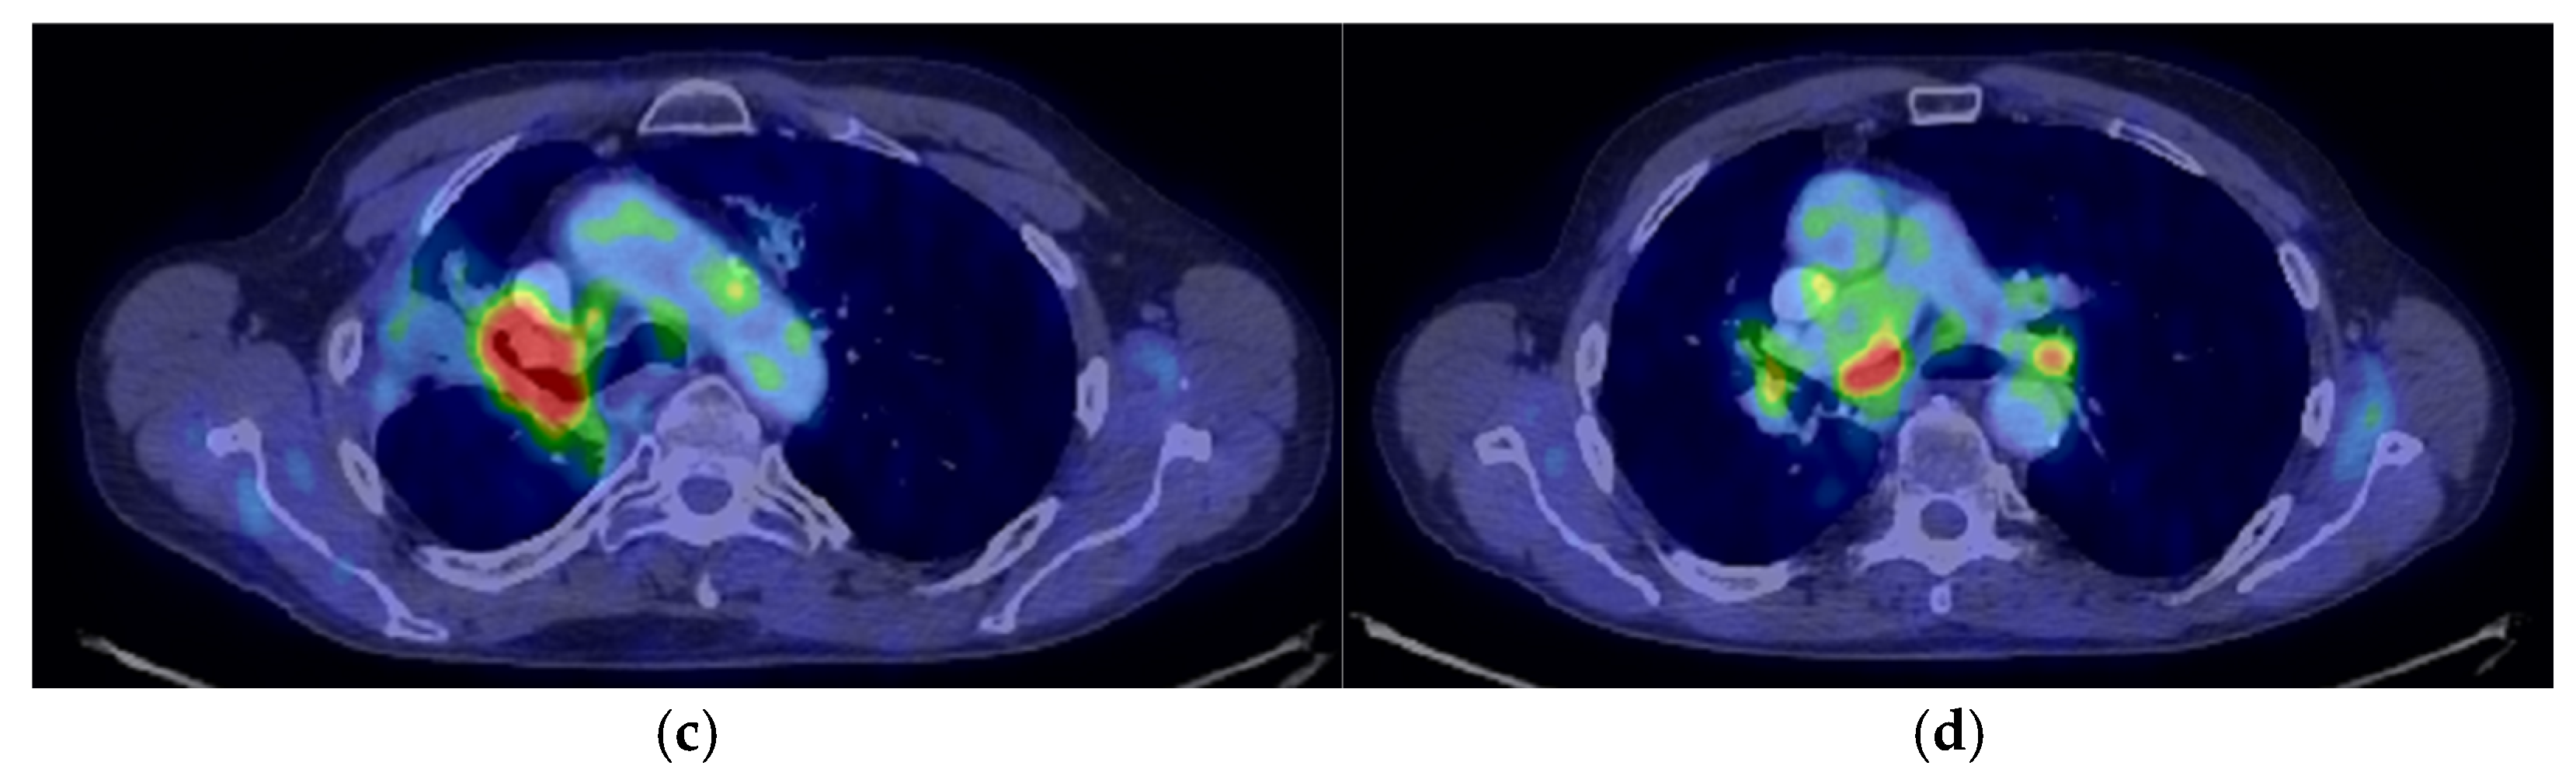

2. Case Presentation

2.2. Monitoring 2022: Oncological Commission 1910/16.08.2022

2.3. Oncological Committee 07/25/2023 Recommended

- Consider rescue re-irradiation (SBRT), taking into account the current primary tumor dimensions of 24 × 34.2 mm on PET CT from 06/2023 and also the total dose previously administered (08–09/2020), the previously applied fractionation, the time between the two irradiations, the cellular repair time and the dose constraints for the organs at risk.

3. Case Results

4. Case Conclusions